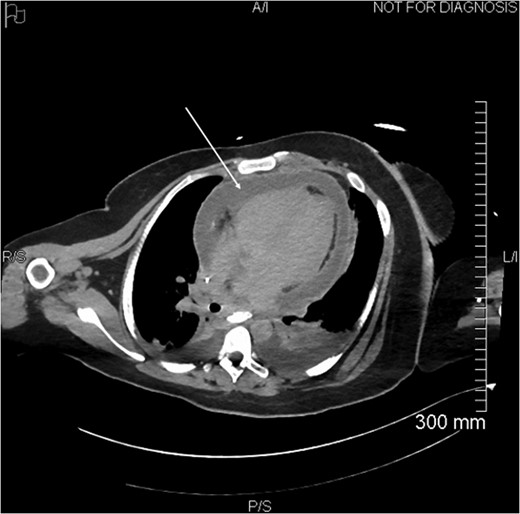

Proximal end of the double pigtail drain externalizes in the pericardium (arrow).

Axial view of opacification on CT showing the externalization of the drain in the pericardium (arrow).